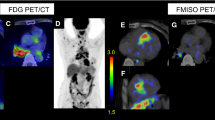

Representative transversal dynamic images of 18F-FAMT and 18F-FDG are shown in Figure 1. The uptake of 18F-FAMT gradually decreased in both granulomas and tumours (Figure 1a). In contrast, the uptake of 18F-FDG gradually increased in both lesions (Figure 1b). The time-activity curves of the mean SUVs of 18F-FAMT and 18F-FDG in each VOI are shown Figure 2. In the tumours, 18F-FAMT showed a shoulder peak immediately after the initial distribution (6 to 15 min and 2 min p.i., respectively), followed by gradual clearance, whereas in the granulomas, 18F-FAMT showed slow, exponential clearance after the initial distribution (2 min; SUV: 1.69 ± 0.25). The dynamic pattern of 18F-FAMT uptake in the tumours was significantly different from that in the granulomas or muscles (Figure 2a, p < 0.001). The dynamic pattern of 18F-FAMT uptake between granulomas and muscles showed no significant differences. The time-activity curves of 18F-FDG in the granulomas and tumours exhibited similar patterns and showed no significant differences (Figure 2b).

Static images of 18F-FAMT-PET and 18F-FDG-PET at 60 min after administration are shown in Figure 3a,b. Visual and SUV assessments of the static images were unable to differentiate tumours from granulomas in all cases, owing to overlaps in 18F-FAMT uptake, although the mean SUV in the granulomas (0.88 ± 0.12) was significantly lower than that in the tumours (1.00 ± 0.10, p < 0.001, Figure 3c). The static images and the mean SUVs of 18F-FDG in the granulomas were similar to those in the tumours (tumour vs. granuloma: 4.25 ± 0.93 vs. 4.00 ± 0.59, p = 0.37, respectively, Figure 3d).

Static 18F-FAMT (a) and 18F-FDG (b) images in rats bearing granuloma and tumour. Transverse, coronal and sagittal images of 18F-FAMT and 18F-FDG (50 to 60 min). White arrow: locations of C6 tumour (right) and granuloma (left). Individual values of SUV for 18F-FAMT (c) and 18F-FDG (d) in granuloma and tumour lesion (50 to 60 min p.i.). Significant differences were determined (**p < 0.005; N.S., not statistically significant).